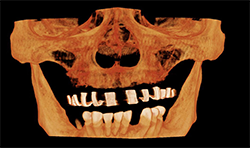

Case 3: 18-year-old woman with cleft for orthognathic surgery

Panoramic and cephalometric radiographs are of limited use due to superimposition of anatomical structures (Figs. 5A, 5B, 5C).

CBCT characterizes the cleft defect more superiorly than 2D imaging (Fig. 6).

The Planmeca Viso G7 CBCT unit and Planmeca Romexis software can stitch two volume scans automatically with one click. The top portion of the skull (Fig. 7A) and the remaining maxillofacial portion (Fig. 6) were stitched to make a single skull volume (Fig. 7B). Multidisciplinary team has been working on this patient. Prosthodontics and oral surgery will plan to manage maxillary alveolar cleft and associated malocclusion following the CBCT images.